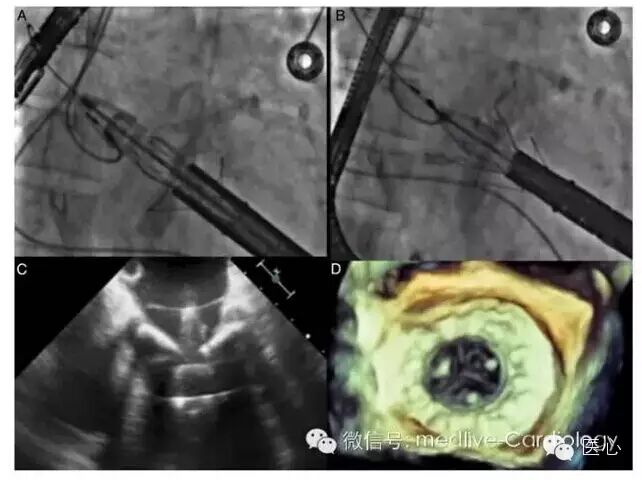

近期ESC颁布了新版感染性心内膜炎指南,鉴于抗生素预防研究均无重大突破,新版指南依然只推荐高危患者在高危牙科手术中应用抗生素预防。指南特别强调了口腔及皮肤卫生与非特异性无菌措施的重要性。诊断技术的进步使得检测血栓的非心脏成像与心脏核成像融合在一起。指南优化了有效抗生素及手术治疗适应症的定义,并强调利用心脏与非心脏成像、微生物学及外科手术学等各种资源对患者进行综合评估。

图4  18氟脱氧葡萄糖正电子成像,患者在Bentall手术后2个月出血葡萄球菌败血症,无超声心动图异常